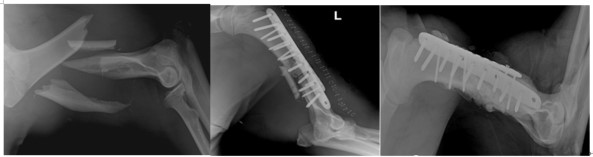

전남대 수의학과 강성수 교수팀은 지난 2018년 버스와 충돌 후 왼쪽 상완골의 비축소성 분쇄골절(non-reducible comminuted fracture of the left humerus)을 입은 반달가슴곰을 야생에서 포획했다.

반달가슴곰이 부상을 입은 상완골은 뼈구조가 복잡하고 두꺼운 근육이 붙어 있어 근육 수축으로 인한 비틀림이 발생하기 쉬워 골절 복구가 어려운 부위다. 특히 곰은 큰 힘을 가해 앞다리를 자주 사용하기 때문에 회복 시 뼈를 단단하게 고정하는 것이 중요하다.

강 교수 팀은 반달가슴곰의 치료를 위해 압축 잠금 플레이트를 이용해 이중 플레이트를 고정하고, 압축 잠금 플레이트에 뼈 형성과 뼈 조직 재생 가속화를 위해 노보시스를 혼합 적용했다. 수술 후 숲에서 재활기간을 거쳐 99일째 무선 송신기를 채워 야생으로 방사했다.